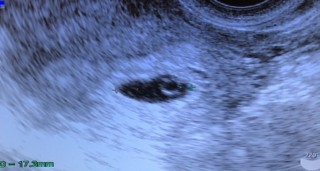

6w2dの時のエコーです。 小さい心拍も同時に確認できました! 形が丸くないのが不安でしたが、婦人科の先生が問題ないと言ってくれました!

6w2dのエコーです。 ピコピコ心拍が確認できて、 まだこんなにちっちゃいのに生きてるんだと思ったら可愛くて仕方ありませんでした。 旦那さんはまだ豆粒みたいでよくわからないみたいですが、やっぱりお腹にいるとなんとなくわかり可愛くて仕方ないです! 次は9wです!ドキドキです。